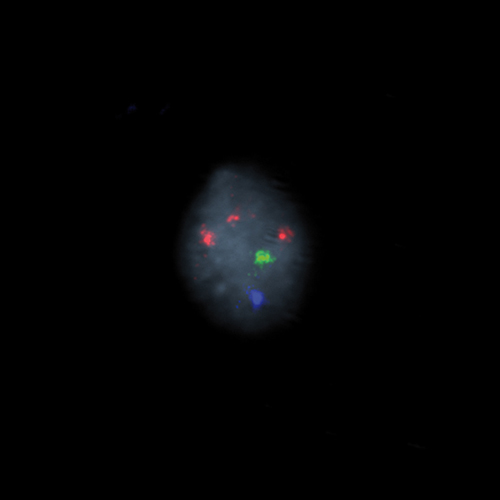

Hybridization of the RCAN1 (21q22), SE X, SE Y probe to a male metaphase spread showing normal pattern (2R1G1B)